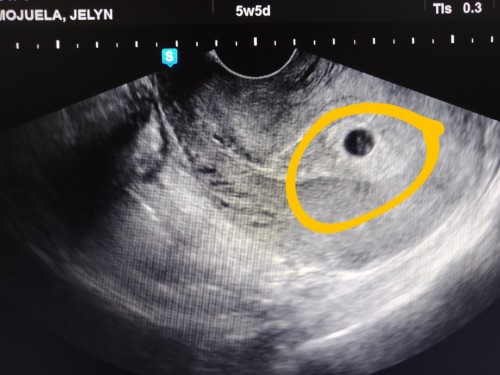

Normal po ba na 4weeks wala pa madetect na fetal pole sa ultrasound??? Nagwoworry kc aq π

sakin 4 weeks thick endometrium lang wala nakita kahit yang bilog na yan. Pero bumalik ako after 2 weeks nakita na si baby and may heartbeat na β€οΈ Kaya wag ka po mastress mommy eat healthy and bed rest ka lang po hanggang sa makabalik ka ulit sa OB mo βΊοΈ